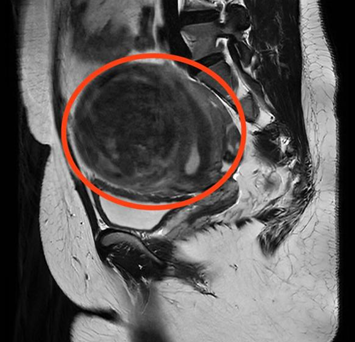

“2年前,肌瘤开始明显增大,今年频繁出现尿频、尿急症状,严重影响了日常生活。”曹女士介绍,为寻求进一步治疗,她来到维多利亚老品牌76696vic妇科门诊就诊。经过B超检查显示,曹女士子宫左侧壁肌瘤内可见102*88*92mm的包块,考虑为子宫肌瘤。面对如此“巨大”的肌瘤,曹女士忧心忡忡,以为只有通过开腹手术才能将其切除,手术过程及术后遗留的疤痕让她既害怕又焦虑。

CT检查显示子宫左侧壁巨大肌瘤

妇产科三区主治医生胡媛耐心地安抚曹女士,并为她详细讲解了治疗方案。“结合您的B超及CT结果,我们只需要进行一个小小的微创手术,就能把肌瘤切掉。而且,手术切口在肚脐眼,这里天然隐蔽,等伤口痊愈以后,几乎不会影响腹部美观。”胡媛医生的这番话,让曹女士悬着的心终于落了地。